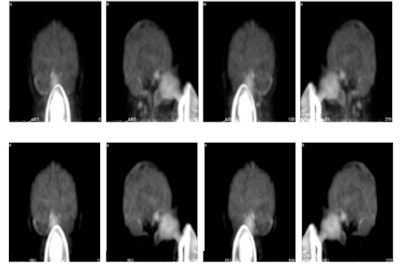

In the scan of the healthy volunteer, the authors reported good image quality when the SSS technique was applied. Again though, introduction of the out-of-FOV correction degraded the images, resulting in inaccurate reconstruction of counts from the carotid arteries and parts of the brain's cerebellum and temporal lobe.